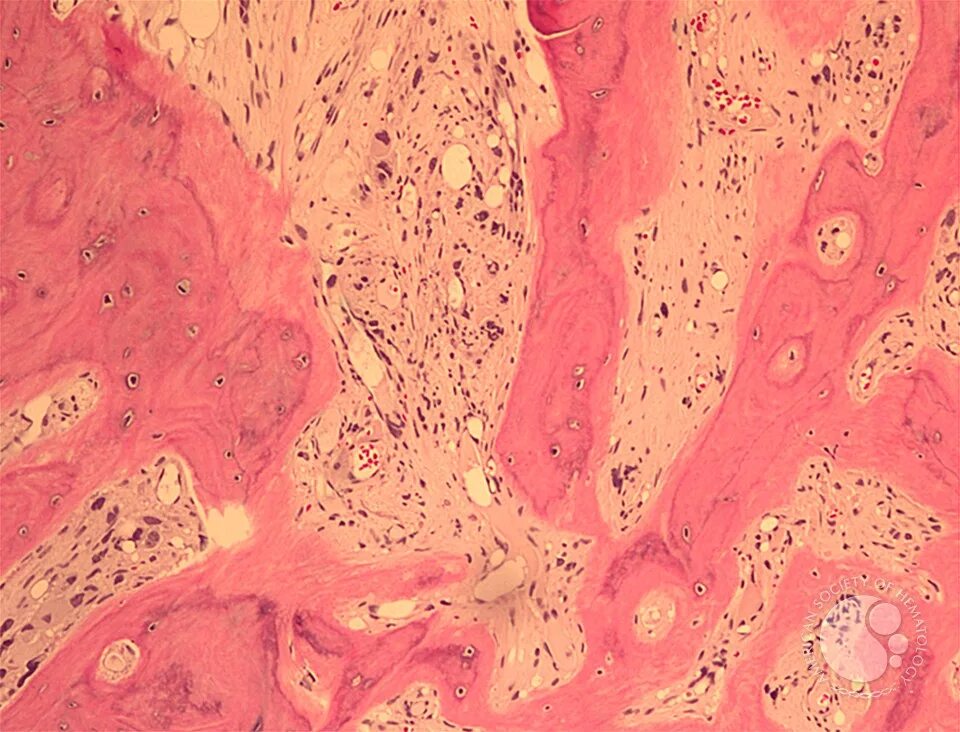

Картина фиброзных изменений